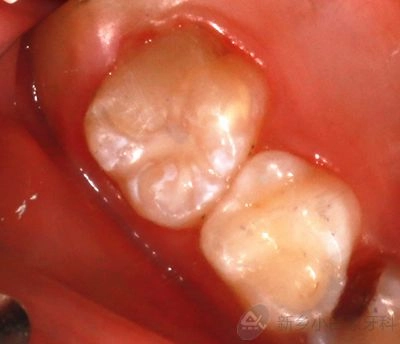

3.png

治疗后